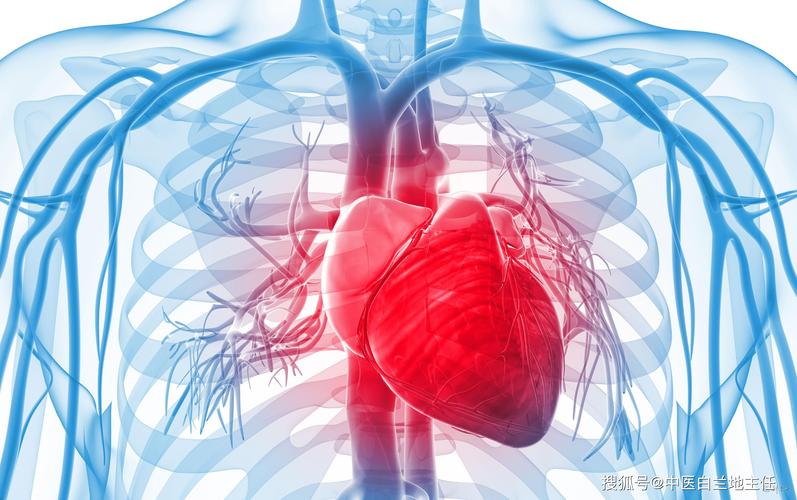

心血管疾病: 这是一种间接的并发症,是由于高尿酸血症与高血压、高血脂、高血糖等代谢紊乱相关联,增加了心血管疾病的风险。

心血管疾病包括冠心病、心肌梗塞、心力衰竭、中风等,都是严重威胁人类健康和寿命的疾病。